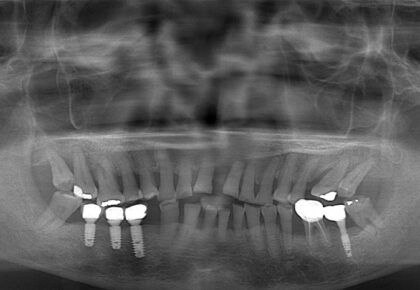

例如這位先生的右下第二小臼齒,在牙周治療前,牙周囊袋的深度有 7 – 8 mm,並且從X光片顯示出有明顯的骨頭缺損。其實就是很有可能需要進入第二階段手術治療的情況。

但僅僅經過了雷射輔助第一階段治療,患者也規律配合改善口腔衛教,後來在追蹤期,我們就發現牙周囊袋已經改善到 2 – 3mm 的正常測量深度值,骨頭的缺損竟然也自然生長癒合!

其實我們很有信心,未來這顆牙齒會因為牙周問題而鬆動的機率非常低,確實後來也保存超過十年!

牙周治療前後,牙齦紅腫的狀況明顯改善

經雷射輔助牙周治療,患齒的牙周囊袋降低至正常的探測深度

治療後,牙周齒槽骨自然再生